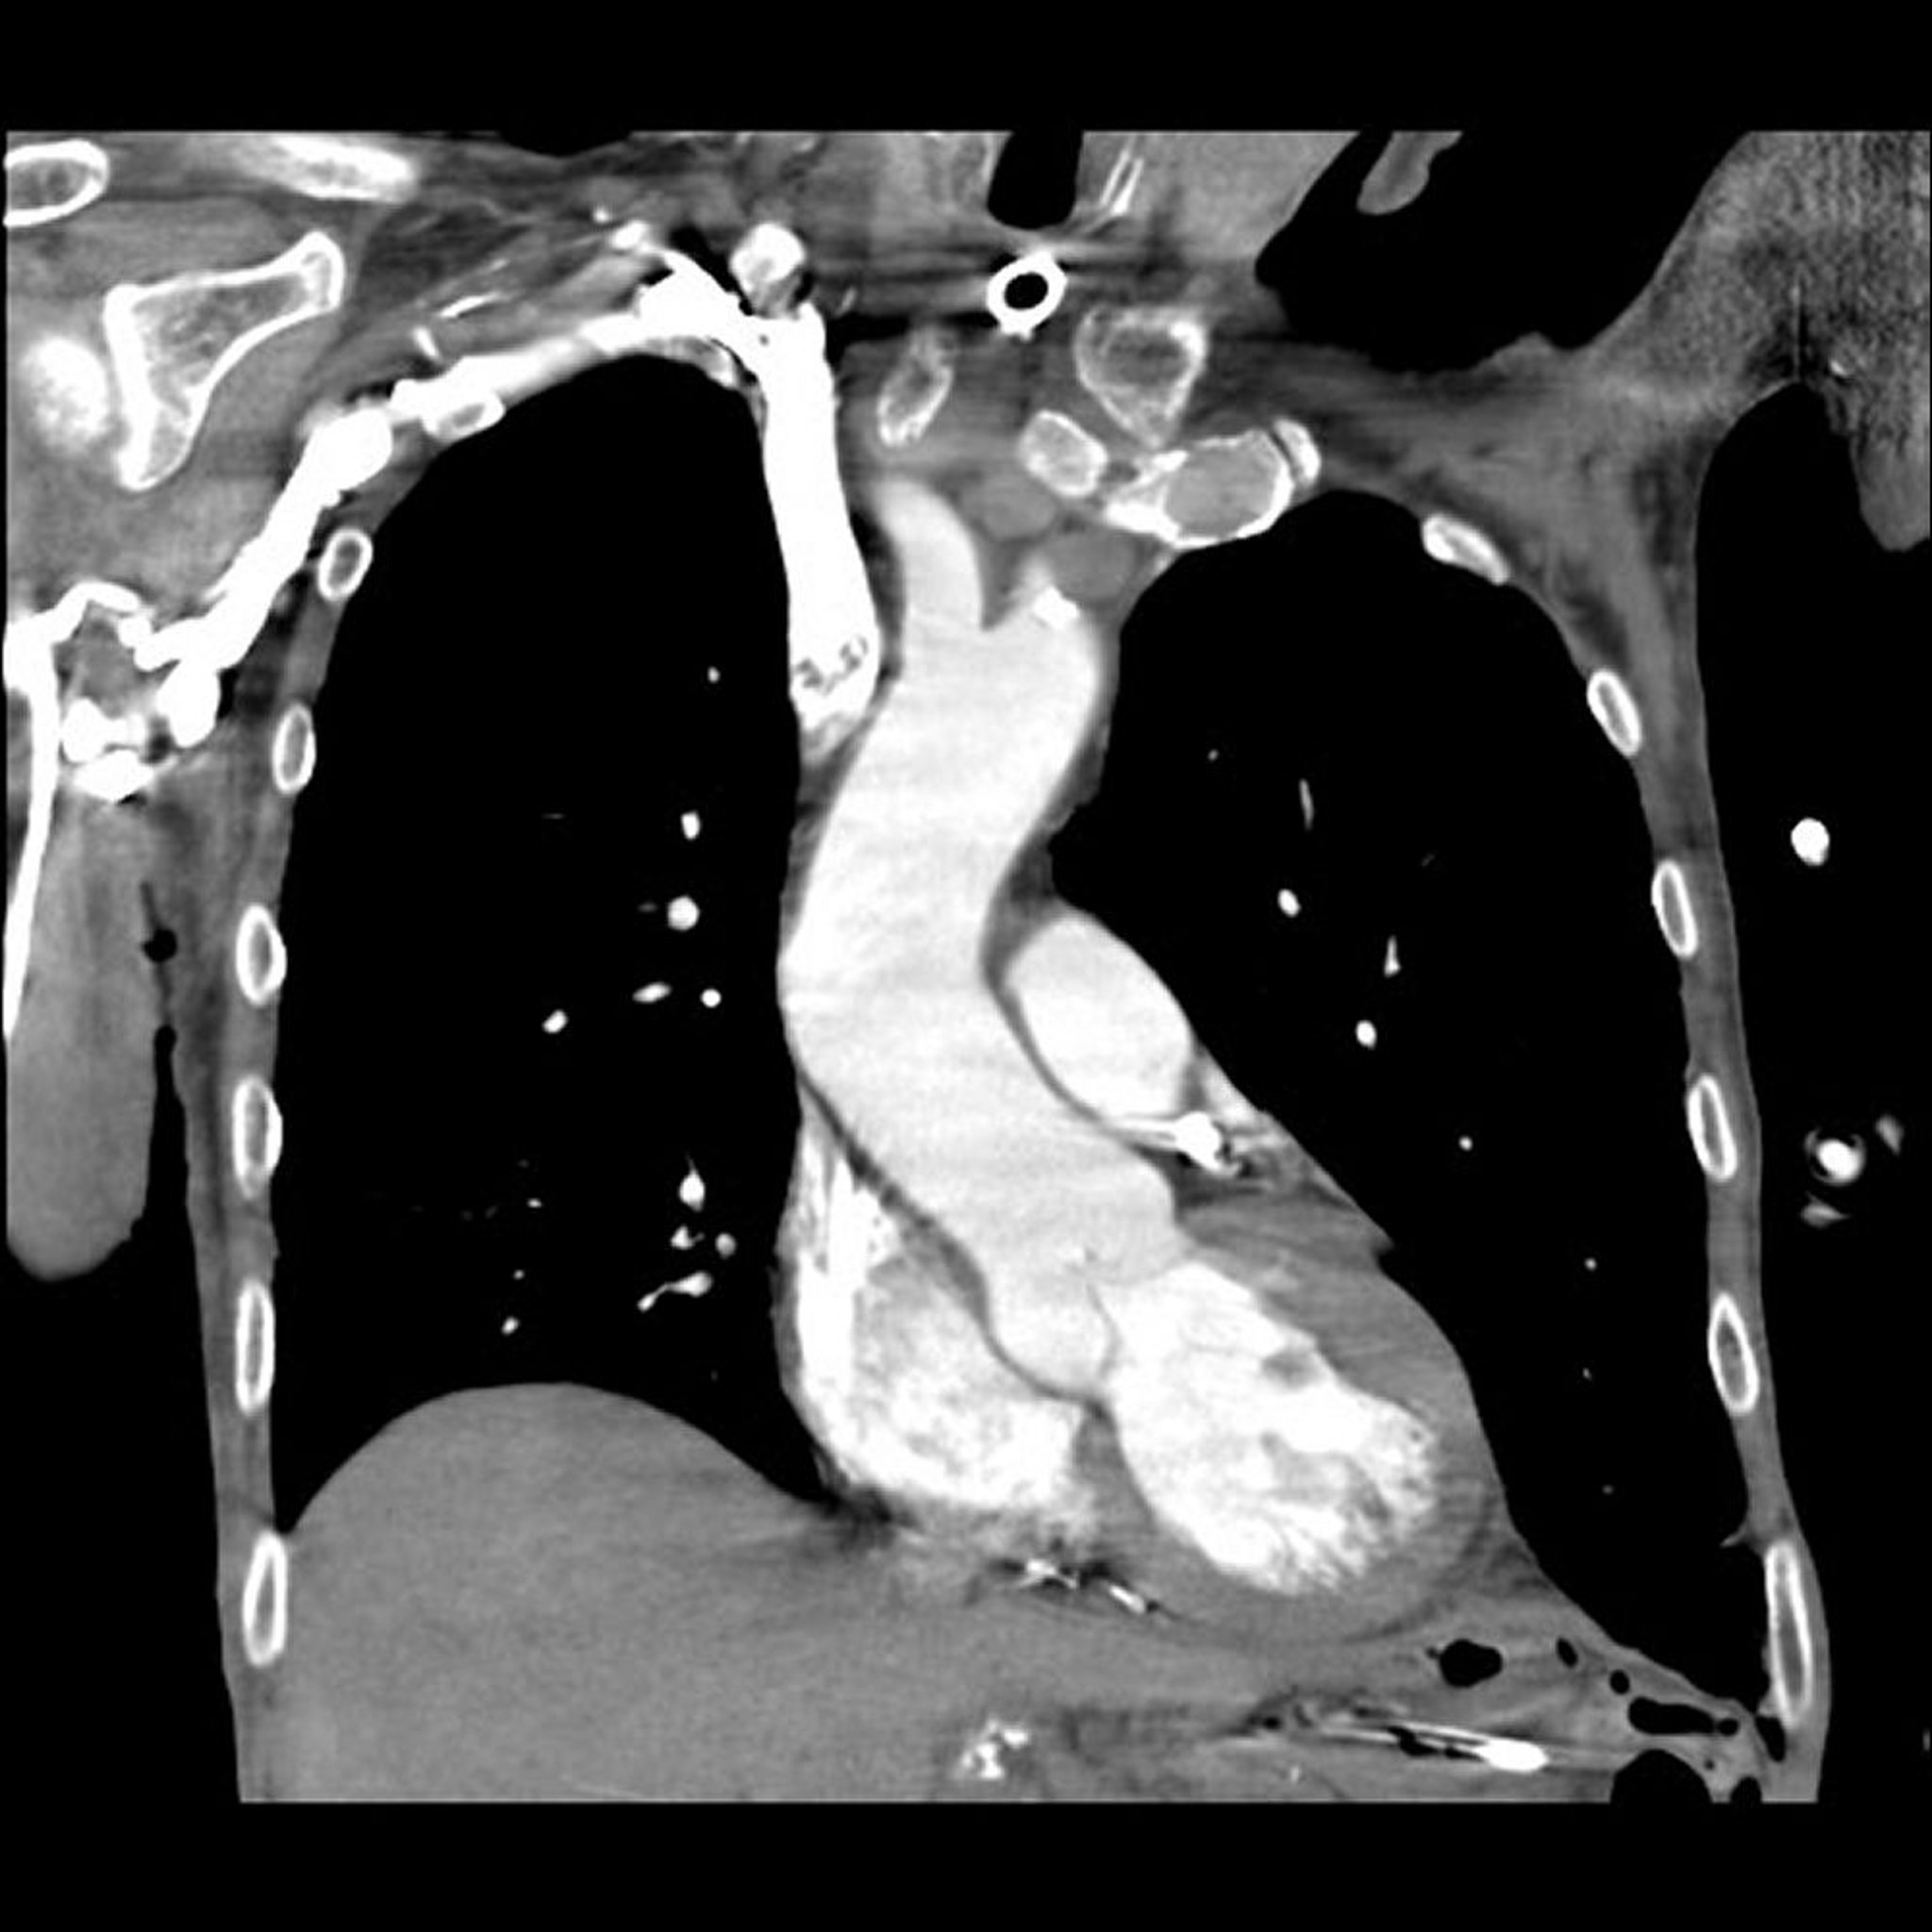

Angiografia pulmonar por tomografia computadorizada (TC)

Imagem fornecida pelo Dr. Mehmet Kocak.